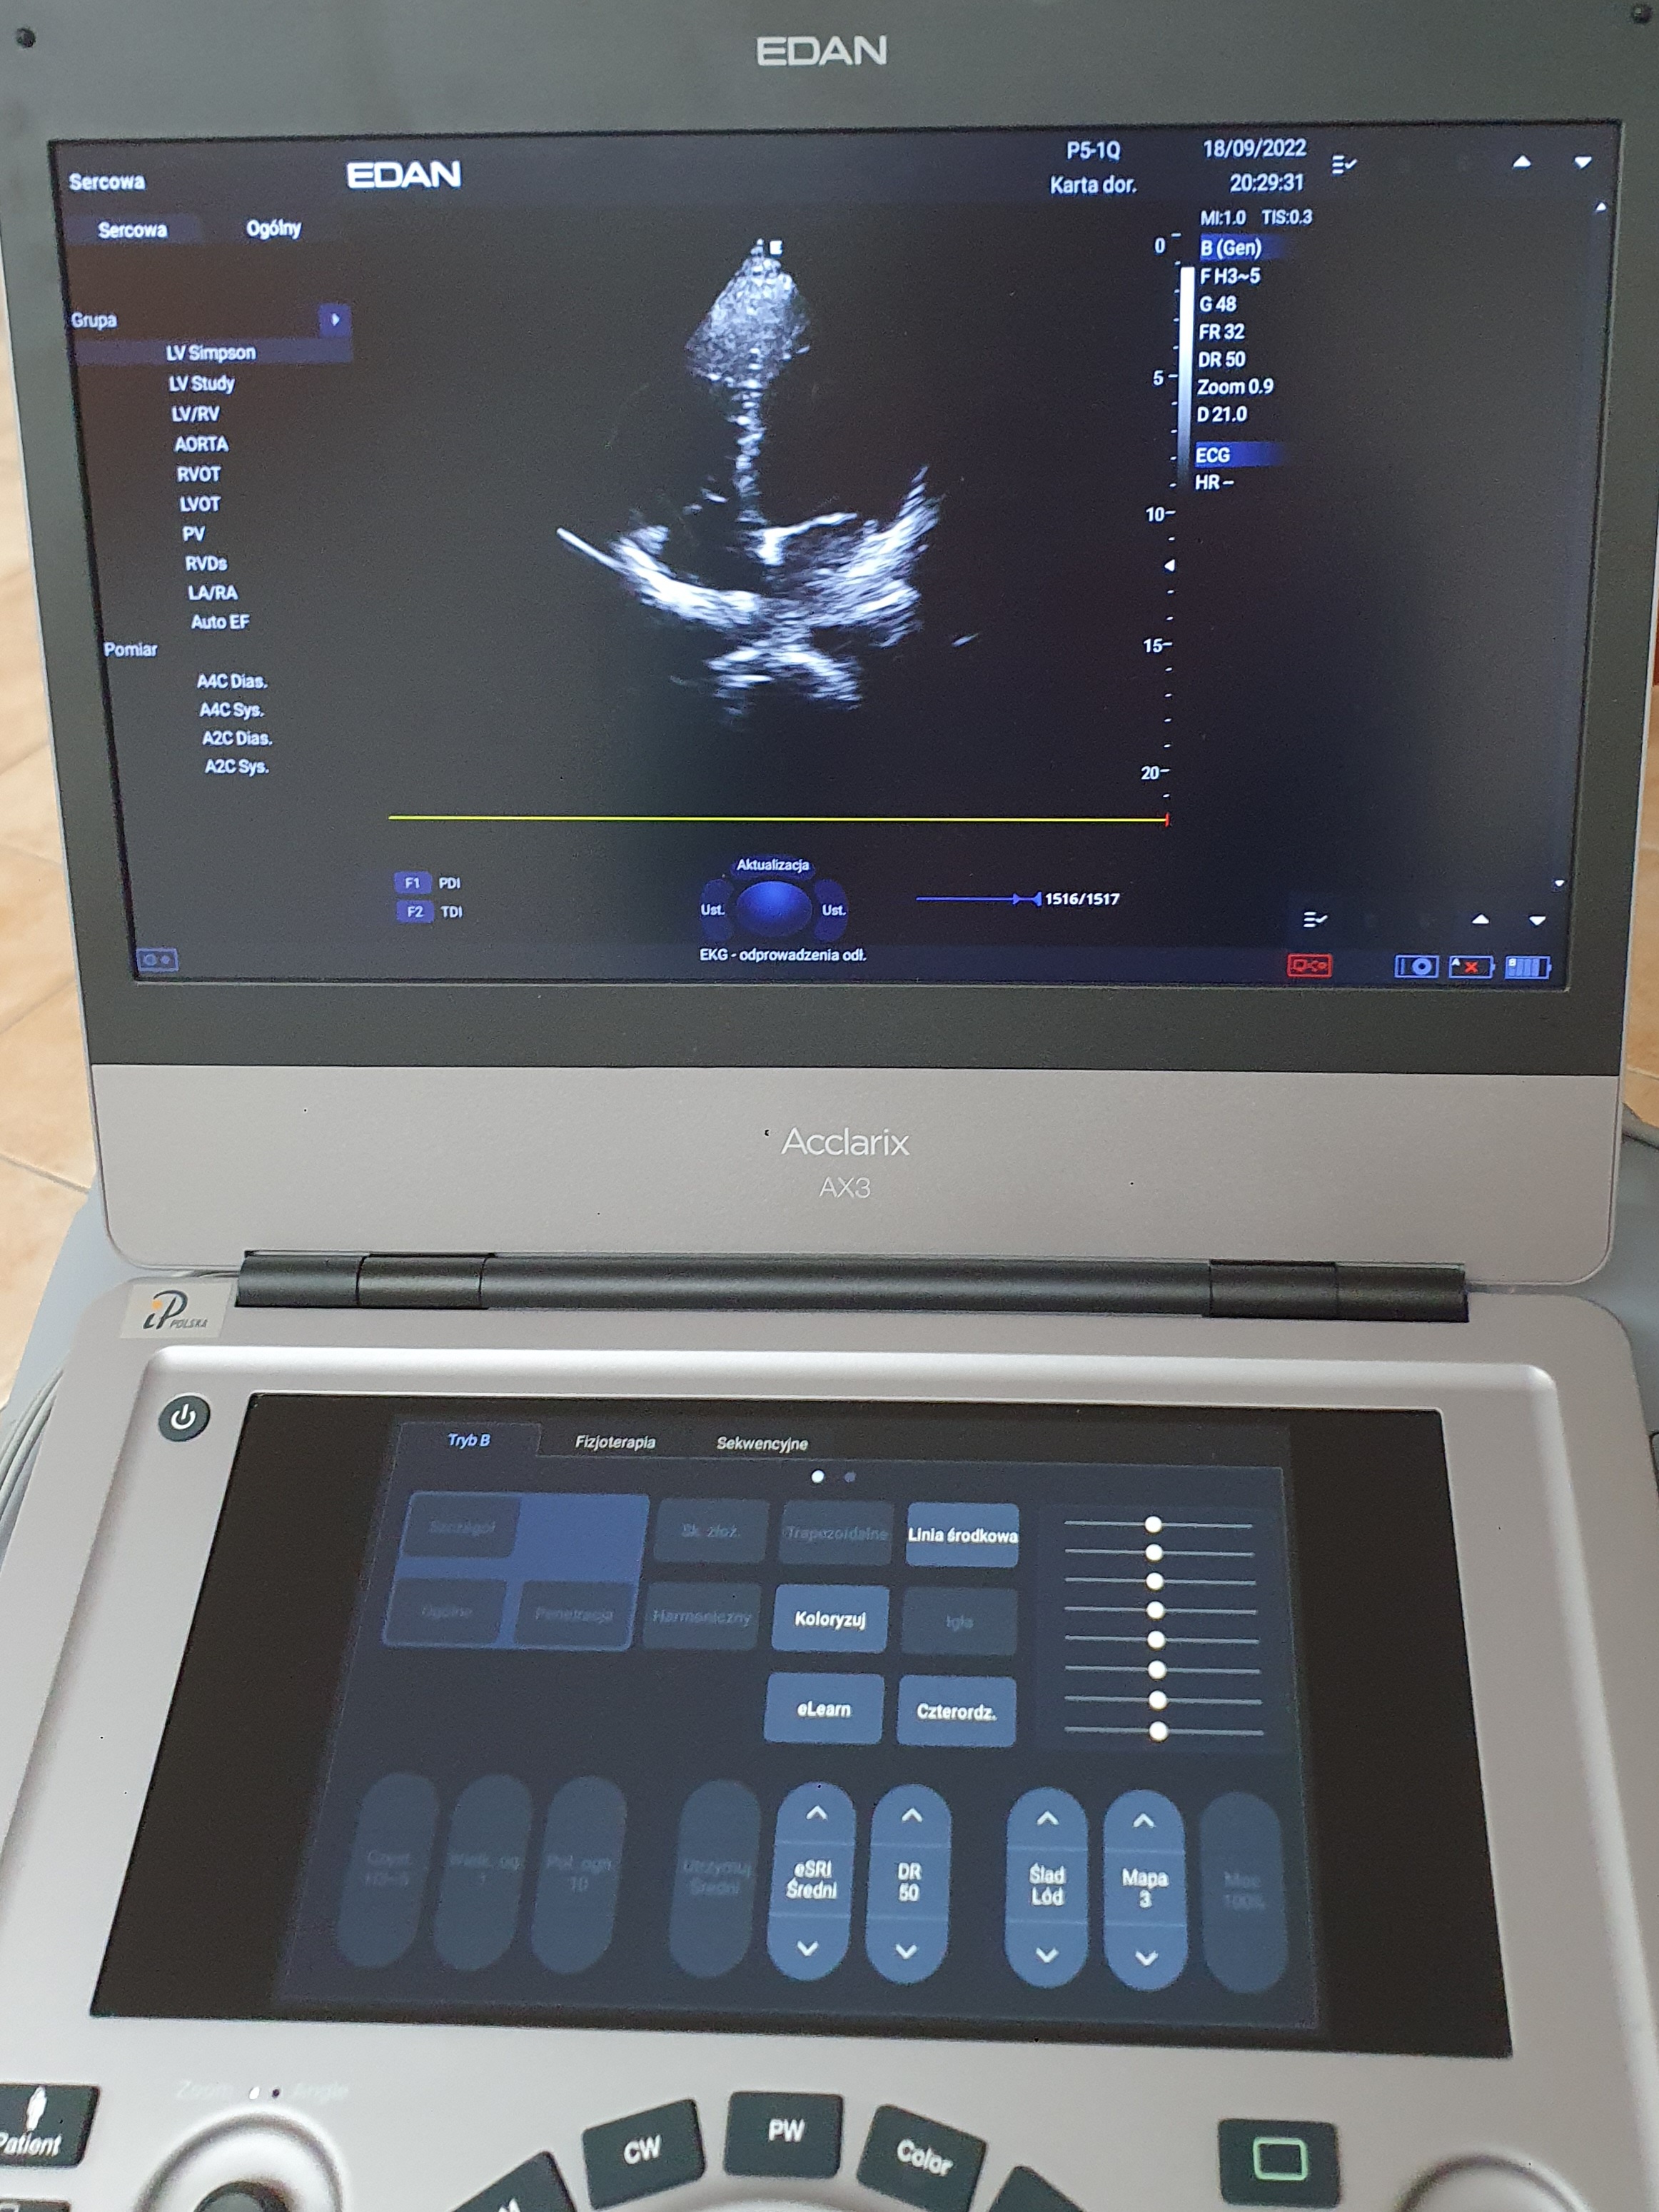

Aparat USG Edan Acclarix AX3, 2 głowice (kardio, convex), stolik

Sprzedam aparat USG Edan Acclarix AX3- kompaktowy, przenośny, wytrzymały aparat USG pracujący na cyfrowej platformie medycznej Android, wyposażony w ekran dotykowy, 2 głowice- kardiologiczna i convex, kabel pacjenta do EKG, dedykowany stolik. Stan idealny, zestaw zakupiony nowy w styczniu 2022 roku za 67 000 zł, jest na gwarancji do stycznia 2024. Używany był sporadycznie. Sprzedaję ponieważ zmieniam profil działalności gabinetu. Acclarix AX3 spełnia wymagania NFZ (ultrasonograf typu I, II i III) oraz Polskiego Towarzystwa Ultrasonograficznego. Wystawiam fakturę